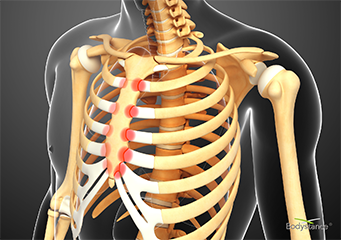

- Free up tight rib cage joints. The Backpod is the only thing we know of that will do this really well, for clear technical reasons - see THE BACKPOD page. This is really important - you can’t take a full breath in if your rib joints are too tight to let you. This is commonly the case with chronic asthma and other lung conditions, rib pain in pregnancy, and persisting pain after chest surgery - see our OTHER CONDITIONS page for more details. All athletic performance will improve if you can get more air into your lungs and better torso rotation, especially swimming, all underwater sports, baseball, cricket, tennis and golf.

Freeing up the tight and immobile rib joints round the back is the essential core of fixing almost all costochondritis, Tietze’s Syndrome and slipping ribs - see our COSTOCHONDRITIS page for more details. The "mysterious inflammation" view of costochondritis is NOT evidence based and generally doesn’t work.